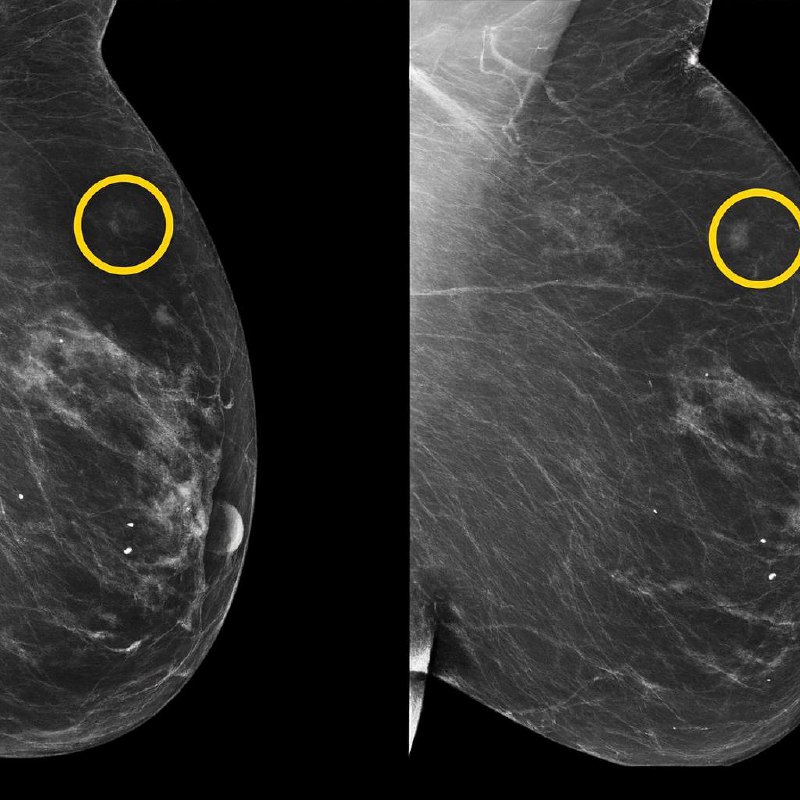

Dnes mamografie zachycuje to, co už je přítomno.

Umělá inteligence však dokáže odhalit to, co se teprve chystá projevit — mikroskopické změny struktury tkáně, skryté děje, kterých si lidské oko — byť odborné — často vůbec nevšimne.